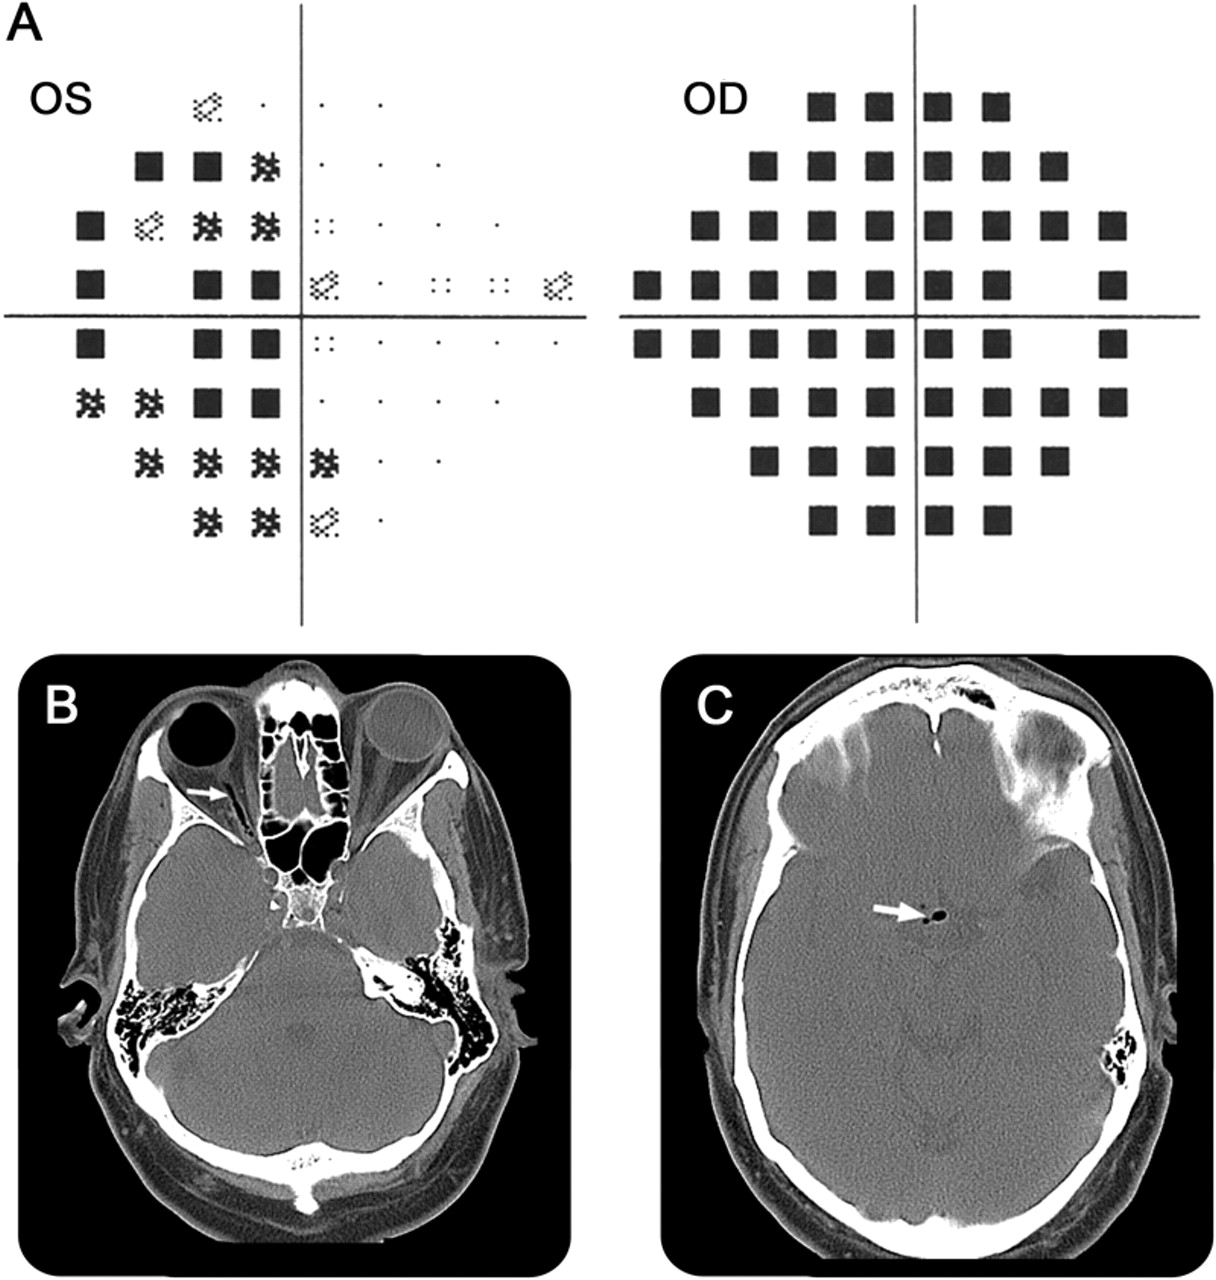

52岁男子发达严重右眼视力丧失,由于视网膜脱离。玻璃体切除术中执行,眼睛,15% C3F8 perfluoropropane气体注入后室。1他是暂时性恢复手势敏锐度。后腔穿刺术进行眼压升高;眼内炎是治疗眼内抗生素。1周后,左眼视力模糊了,完整的中央敏锐度和赤字(时间字段图)。CT成像演示了迁移的眼内气体为视神经和交叉。交叉的气动retinopexy视力丧失是一种罕见的并发症。

视野测量测试和CT成像

(一)视野测量测试证明减少敏感性在时间领域的左眼视网膜脱离(侧)。(B, C) CT扫描显示在正确的全球天然气,跟踪从右侧视神经视交叉(箭头)。天然气也存在于侧脑室。